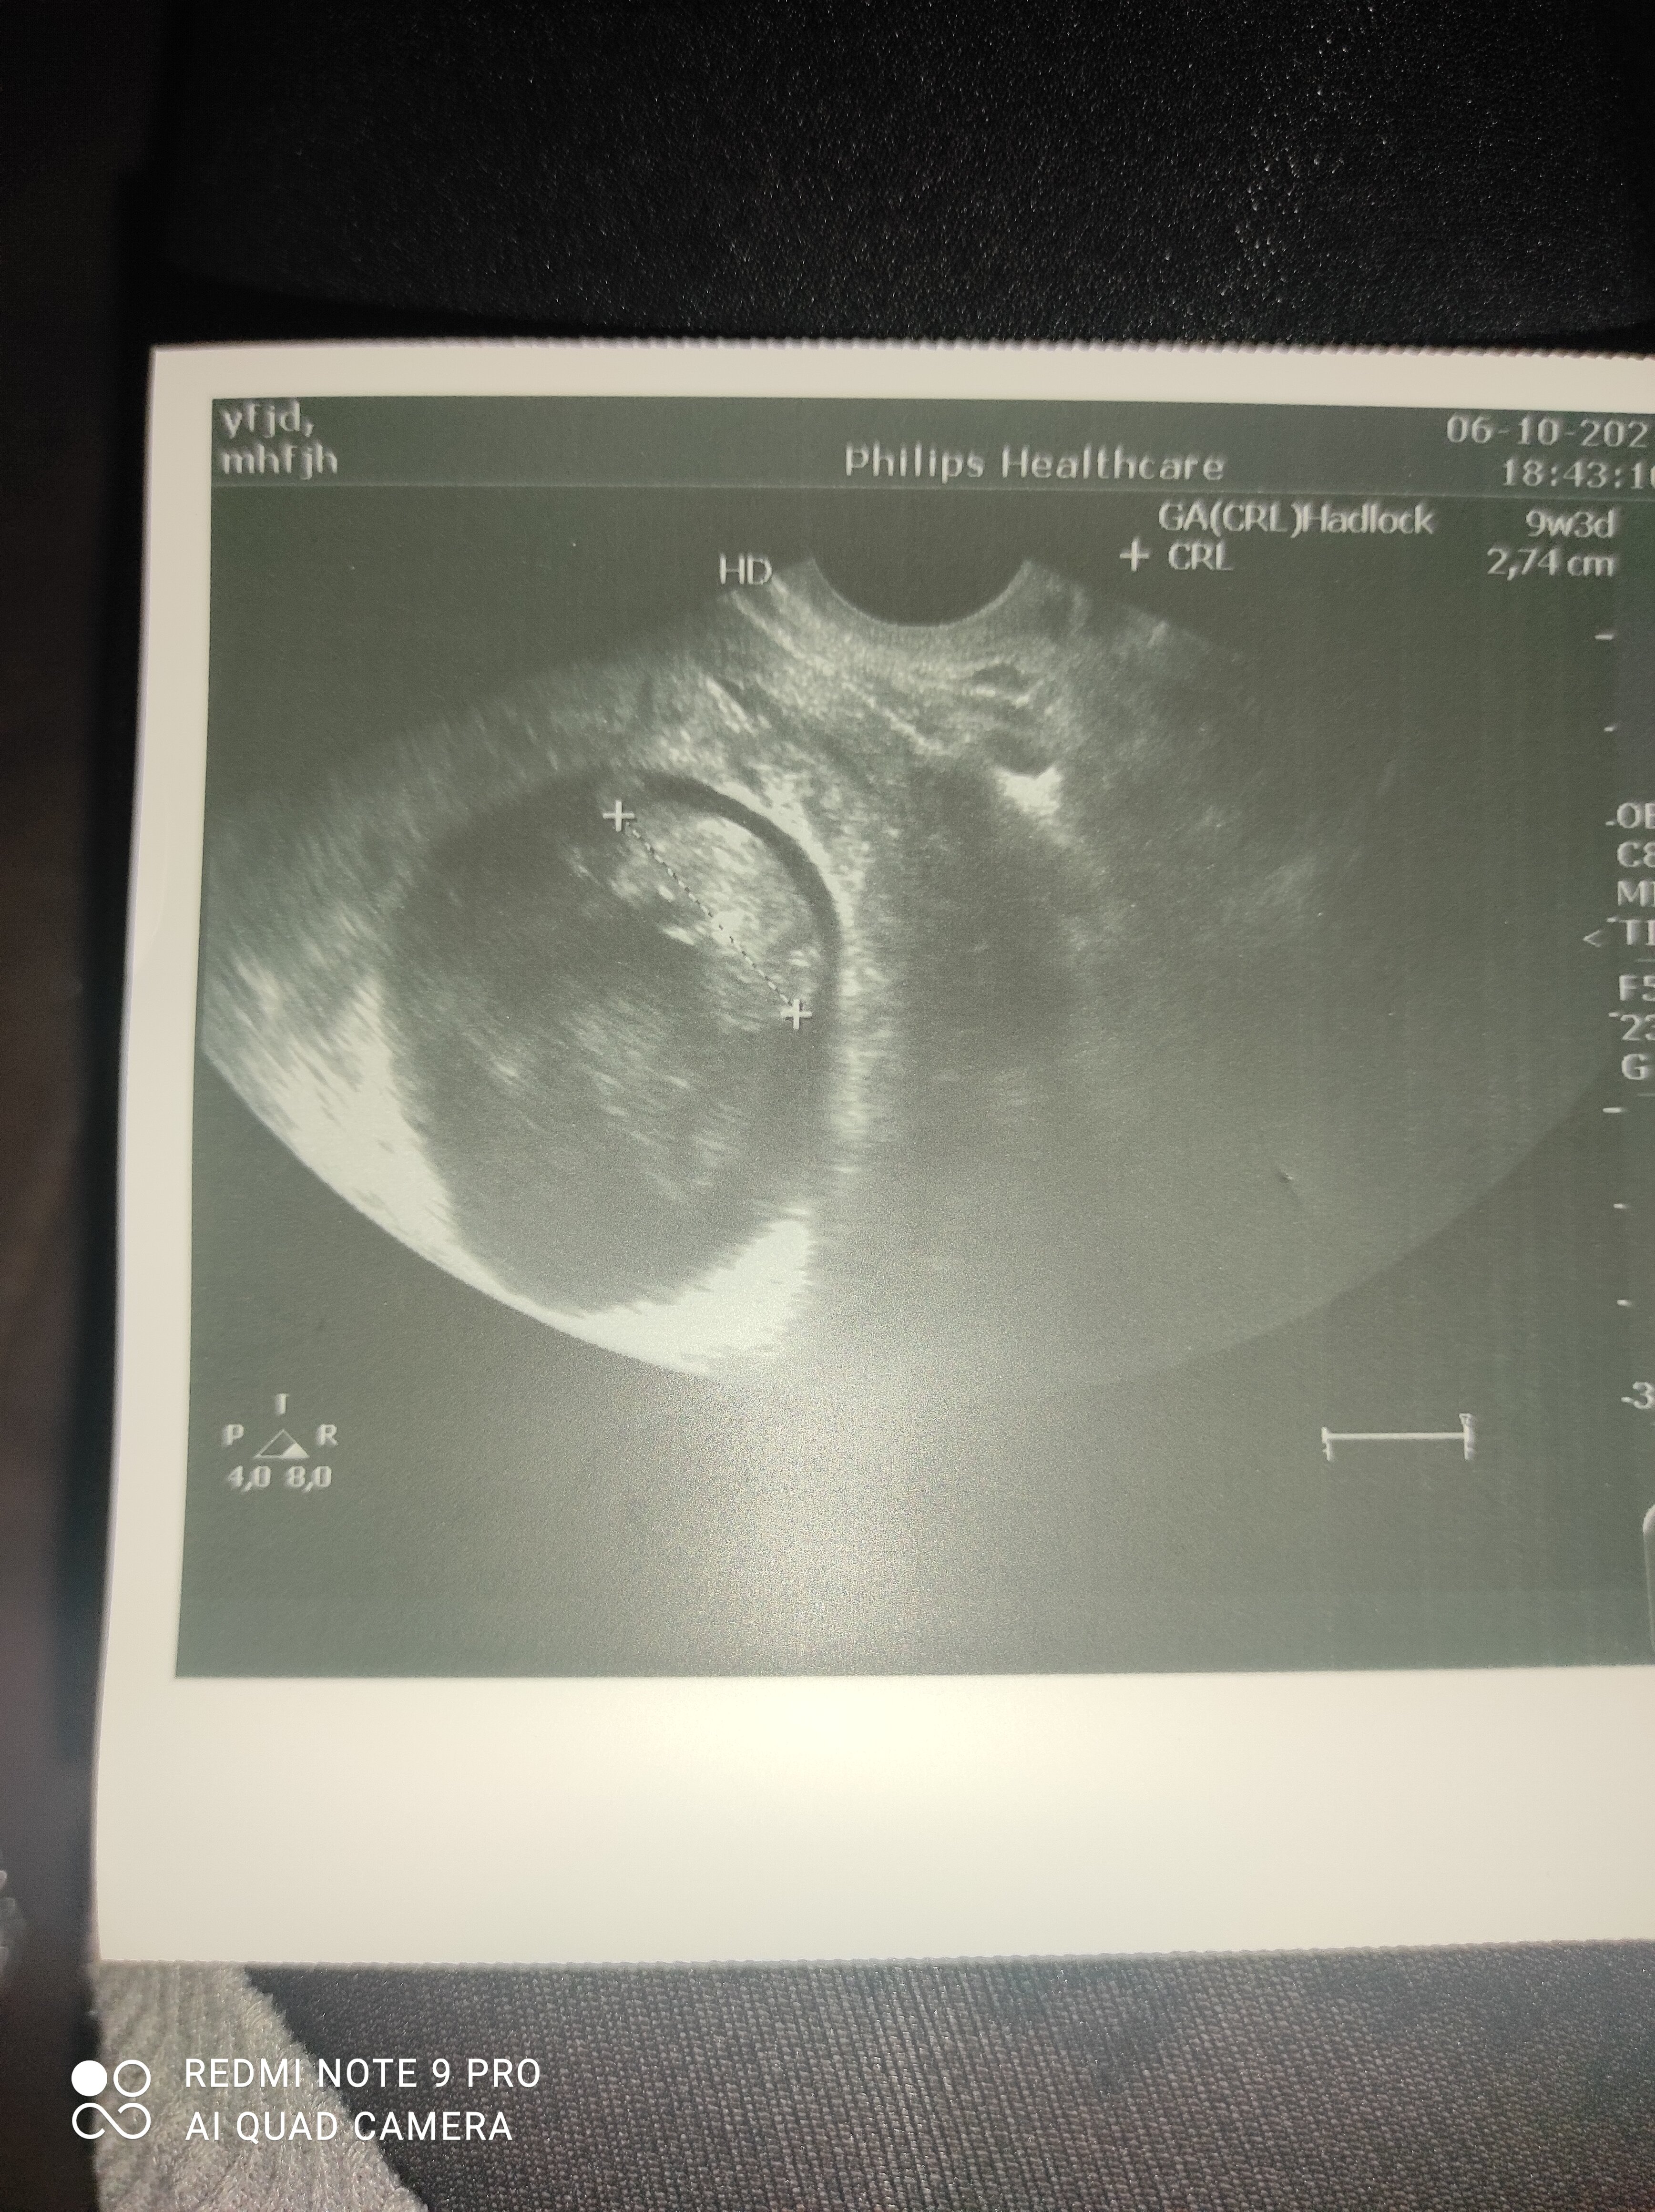

A ja wczoraj rozmawiając z lekarzem się tak wystraszyłam bo mam te ciała ketonowe w moczu a nie powinno ich być w ogóle i mi powiedział że one przez łożysko przechodzs i uszkadzają mózg dziecka a ja te badania i tak zrobiłam je dwa tygodnie później bo wcześniej lekarza nie było a nie wiem od kiedy je mam

i wyłam wczoraj wieczorem bo nie dość że zmiana w diecie dosyć drastyczną bo praktycznie nic nie mogę to jeszcze taka informacja a jeszcze czuje się przeziębiona a we wtorek mam wizytę USG na której mi mega zależy .. staram się wykurować